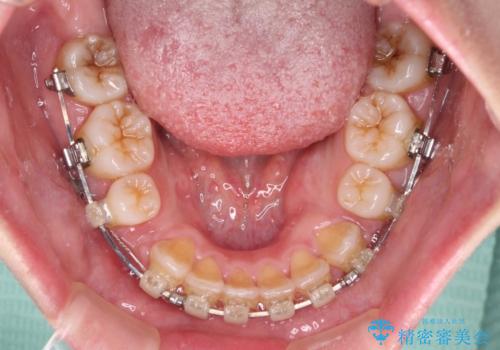

- 矯正装置

- クリアブラケット

- 治療期間

- 3年

- 治療回数

- 30回以上